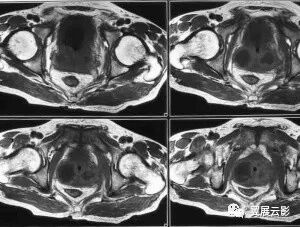

前列腺脓肿不同病理时期 MRI 表现也不同, 在影像学表现上呈多样性,MRI 表现取决于脓肿腔内结构及脓肿壁结构,典型前列腺脓肿脓腔为坏死液化组织、脓肿壁为纤维肉芽组织,脓肿常呈类圆形,脓腔 T1WI 呈低信号,T2WI 呈高信号,脓肿壁 T1WI呈等或稍高信号,脓腔内分隔T2WI 呈低信号,增强脓肿边界清楚,壁及分隔明显强化,分隔可不完整,脓肿壁厚薄均匀,边缘光滑,脓腔不强化。脓液内有炎性细胞和纤维素的碎屑时,T1WI 呈点、斑状高信号,T2WI 高信号区有不规则稍低信号。前列腺脓肿壁早期由炎症充血带构成,增强脓腔周围厚环状中等度强化,边界欠清。脓肿壁强化程度及边界反映了脓肿形成不同时期,多发前列腺脓肿,因脓肿形成病理时期不同,脓肿壁强化表现不同。